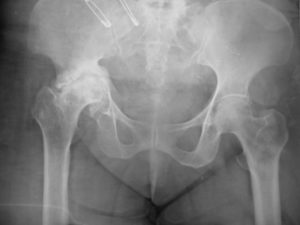

Hip replacement is most commonly recommended for severe osteoarthritis, but it’s sometimes used for inflammatory conditions such as rheumatoid arthritis or ankylosing spondylitis or for problems with development of the hip during childhood. Hip surgery may also be needed for fractures of the hip, including those resulting from osteoporosis. Your doctors will always try other measures before suggesting a hip replacement – for example, painkillers, physiotherapy and/or walking aids, or occasionally a steroid injection into your hip joint. Typically, a diagnostic X-Ray shows whether a hip replacement is required or not. The doctor will also assess your fitness for surgery based on several parameters.

This is performed for painful conditions of the hip like osteoarthritis, rheumatoid arthritis, avascular necrosis, certain fractures etc. Modern hip replacements make use of materials like titanium, ceramics, and cobalt-chrome that make them tough and durable. Age is not generally a concern when considering someone for a hip replacement as long as they have the right indication. Ten year survivorship in general is more than 95% for most established prostheses.